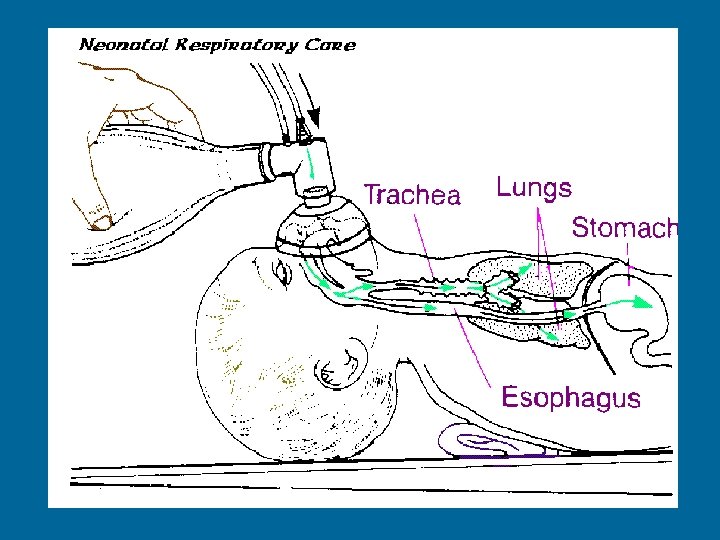

Lesson 3: Insertion of Orogastric Tube Measuring correct length © 2000 AAP/AHA